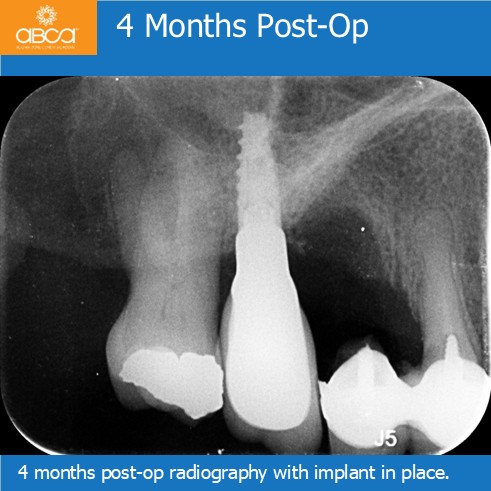

Initial CBCT images show the estimated ridge height as 1-2mm below the sinus. The BY2 diamond milling bur breaks through the sinus floor. Following the Augma Lift™ technique protocol, membrane elevation and augmentation are performed. Radiography shows implant placement 4 months post-op in newly formed bone.